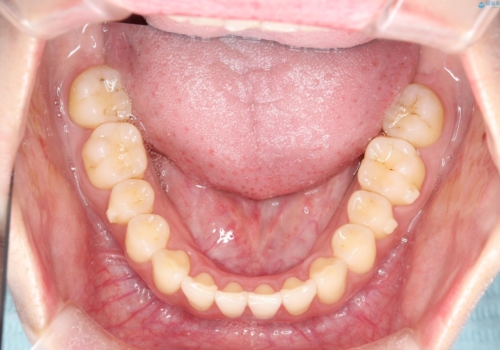

初診時の歯並びの状態としては、上下にガタガタがある状態であり、特に上の前歯(左上1番)の捻じれを最も気にしていらっしゃいました。

前歯の捻じれを改善するためにスペースを作る必要があり、前歯の歯の間を削って簡単に直す方法もありますが、奥歯のズレが認められたため、大臼歯後方のスペースを利用し、根本的な原因からしっかりと治療を行いました。